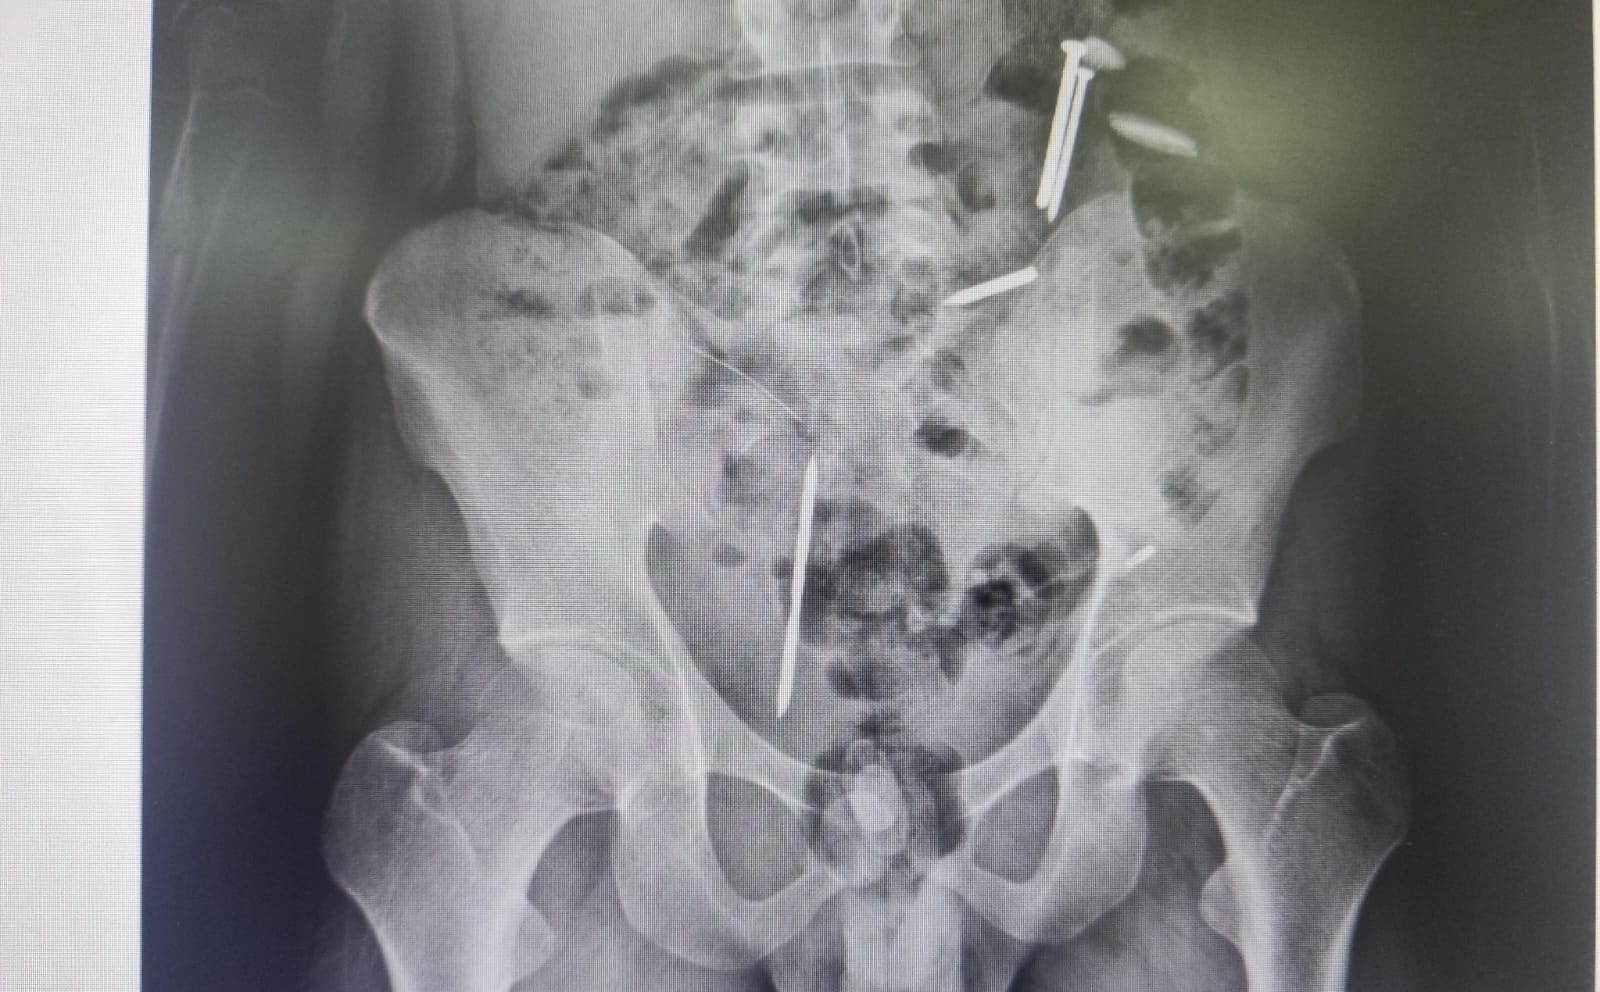

Berdasarkan hasil rontgen dan CT scan yang dilakukan di RSJ Lawang, Malang, tim medis menemukan dua benda menyerupai paku, tiga benda logam, serta gumpalan hitam misterius di area perut Vemas. Temuan ini memaksa tim medis untuk memprioritaskan tindakan bedah sebelum melakukan penanganan kejiwaan.

“Saat proses rontgen, ditemukan benda-benda asing di dalam tubuhnya. Ada yang menyerupai paku dan logam lainnya. Bahkan ada gumpalan berwarna hitam yang belum bisa kami pastikan identitasnya,” ujar Roni saat dikonfirmasi melalui sambungan telepon, Rabu (8/4/2026) malam.

Roni menjelaskan, pihak RSJ Lawang menyarankan tindakan operasi besar untuk mengeluarkan benda-benda tersebut. Hal ini dilakukan guna menghindari risiko infeksi organ dalam atau komplikasi medis lainnya yang dapat mengancam nyawa pasien selama masa perawatan kejiwaan.